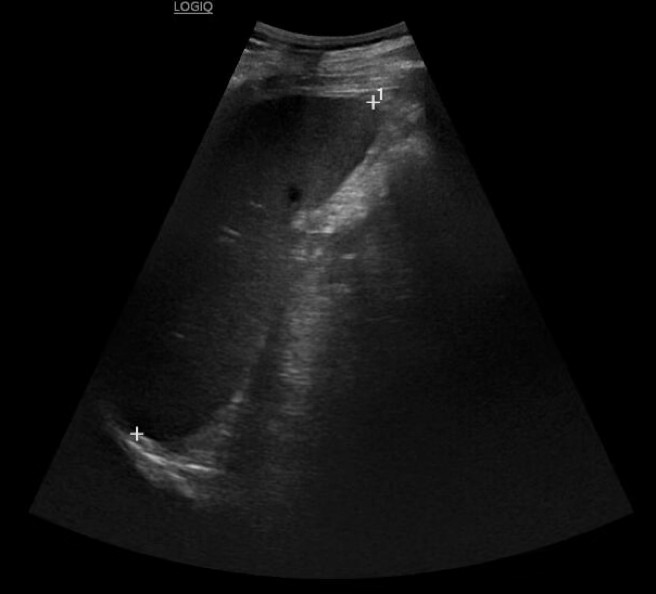

La ecografía abdominal urgente muestra engrosamiento parietal del colon descendente-sigma-recto, aumento de ecogenicidad de la grasa pericólica e hiperemia, compatibles con colitis izquierda.

La ecografía abdominal urgente permitió identificar precozmente un proceso inflamatorio colónico, orientar el diagnóstico diferencial y priorizar la realización rápida de tomografía, detectando una complicación abscesificada. Este caso destaca el valor de la ecografía en Medicina de Familia como herramienta accesible, resolutiva y clave para mejorar la seguridad, optimizar derivaciones y reducir tiempos asistenciales.